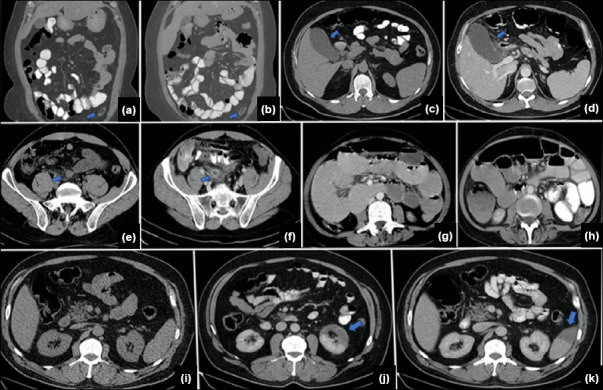

Methods: A retrospective analysis was conducted on patients who presented with acute abdominal symptoms to the emergency department between January 1, 2013 and May 30, 2023, and underwent abdominopelvic CT scans in the acute setting. Among this cohort, 149 patients had repeat abdominopelvic CT scans during the same admission and were classified into five groups based on findings: Group A (no change in diagnosis), Group B (confirmation of suspected initial diagnosis), Group C (disease progression), Group D (disease regression), and Group E (new diagnosis).

Results: The mean age of the cohort was 51.5+-18 years (range: 19-92). The average interval between initial and repeat CT scans was 40.9+-59.05 hours (range: 0.5-238). The number of patients in each group was as follows: Group A (n=21), Group B (n=60), Group C (n=32), Group D (n=25), and Group E (n=11). Partial bowel obstruction was the most common finding (27%, 41/149), with 72% (18/25) of Group D showing regression on follow-up CT. The "wait and follow-up" approach significantly guided management decisions for partial bowel obstruction (p<0.01).

Conclusion: This study emphasizes the importance of the "wait and repeat CT" strategy in enhancing diagnostic accuracy and guiding clinical management for patients with acute non-traumatic abdominal complaints. Follow-up CT scans were particularly effective in identifying conditions such as partial bowel obstruction.